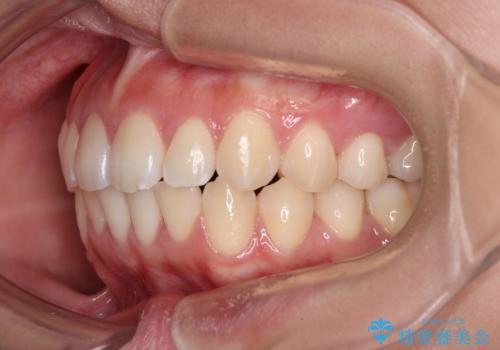

1年弱の短期間で、望み通りのスッキリとした口元に仕上げることができました。